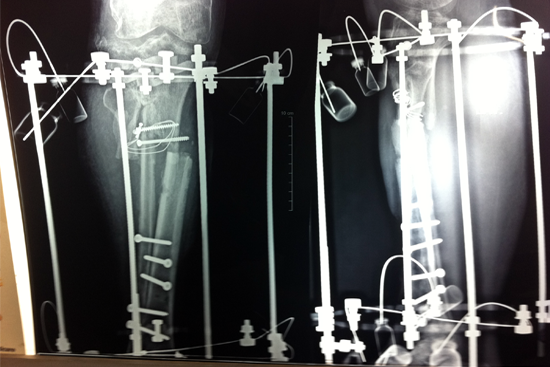

Tibialisation Of Fibula